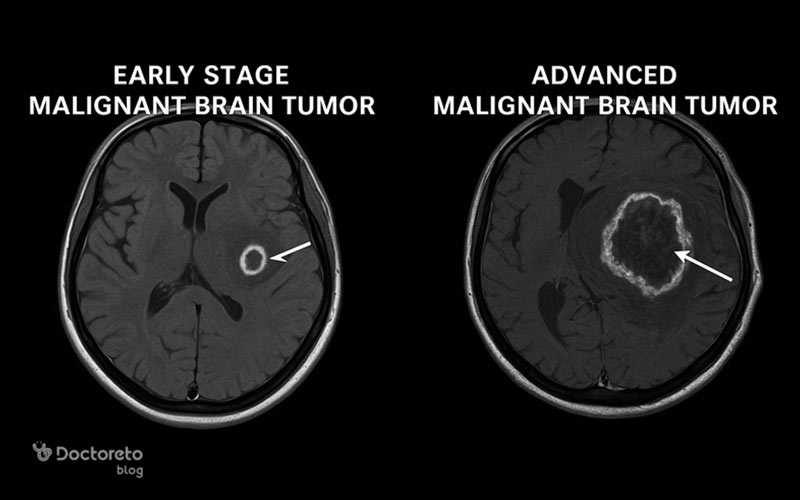

شناخت تصویری تومور مغزی به فهم مسیر تصمیمگیری درمان کمک میکند. تومور مغزی بدخیم در مراحل اولیه ممکن است کوچک، با درگیری محدود و علائم خفیف باشد؛ اما در مراحل پیشرفته معمولاً بزرگتر، نامنظم و همراه با فشار بر ساختارهای اطراف دیده میشود. عکسها با امآرآی و سیتیاسکن تهیه میشوند تا محل دقیق، اندازه و میزان گسترش مشخص شود و بتوان تفاوتهای مرحلهای، نواحی نکروزه و تغییرات بافتی را دید. در پیگیری، تصاویر برای ارزیابی اثر درمان و احتمال عود کاربرد دارند. پیش و پس از جراحی نیز تصویربرداری به برنامهریزی و سنجش میزان برداشت کمک میکند. هدف این نوشته، ارائهٔ تصویری روشن از عکسها، تفاوت مراحل، روشهای رایج تصویربرداری و نقش آنها در پیگیری درمان است. در این مطلب از دکترتو، با عکس تومور مغزی بدخیم، تفاوت مراحل، روشهای تصویربرداری و تصاویر قبل و بعد از جراحی آشنا میشوید.برای تفسیر دقیق نتایج تصویربرداری و تصمیمگیری درباره روشهای درمان، مشاوره با دکتر مغز و اعصاب ضروری است؛ زیرا این متخصصان با بررسی تصاویر امآرآی و سیتیاسکن میتوانند ماهیت تومور، میزان درگیری بافتی و بهترین مسیر درمانی را مشخص کنند.

عکس تومور مغزی بدخیم در مراحل اولیه

تصاویر مربوط به تومور مغزی بدخیم معمولاً با استفاده از روشهای پیشرفتهای مانند ام آر آی و سی تی اسکن تهیه میشوند. این تصاویر به پزشک کمک میکنند تا محل دقیق، اندازه و میزان گسترش تومور را در بافت مغز بررسی کند. همچنین، از این عکسها برای ارزیابی پیشرفت بیماری، تأثیر درمان و احتمال عود تومور در مراحل بعدی استفاده میشود. در تصاویر، تومورهای بدخیم معمولاً با مرزهای نامشخص، رشد سریع، تغییر در تراکم بافت مغز و وجود نواحی نکروزه (مرده) قابل شناسایی هستند.

در مراحل اولیه، تومور مغزی بدخیم معمولاً اندازهای کوچک دارد و ممکن است تنها بخش محدودی از بافت مغز را درگیر کند. در تصاویر ام آر آی و سی تی اسکن، این نوع تومور بهصورت تودهای کوچک با تراکم متفاوت نسبت به بافت طبیعی مغز دیده میشود. در این مرحله معمولاً ورم یا فشار شدیدی روی نواحی اطراف مغز وجود ندارد و بیمار ممکن است تنها علائم خفیفی مانند سردردهای گهگاهی یا اختلال تمرکز را تجربه کند. گاهی در ضایعات کوچک اما شدیدا پرخطر علائم شدید است. تشخیص زودهنگام در این مرحله اهمیت زیادی دارد، زیرا درمان مؤثرتر و کمتهاجمیتر است و شانس بهبودی افزایش مییابد.

پزشکان با مقایسه عکسهای اولیه و آزمایشهای تکمیلی، نوع دقیق تومور را مشخص میکنند. در صورت شروع بهموقع درمان، احتمال کنترل رشد تومور و جلوگیری از گسترش آن به سایر بخشهای مغز بسیار بیشتر خواهد بود.

عکس تومور مغزی بدخیم ابزار مرکزی برای تشخیص، سنجش شدت درگیری و برنامهریزی درمان است. در مراحل اولیه، تصاویر معمولاً تودهای کوچک با تفاوت تراکم کم نسبت به بافت طبیعی را نشان میدهند و علائم میتواند خفیف باشد؛ در مراحل پیشرفته، توده بزرگتر و نامنظم است و فشار بر ساختارهای اطراف و تورم دیده میشود. امآرآی و سیتیاسکن امکان تعیین محل، اندازه و گسترش را فراهم میکنند و با مقایسهٔ دورهای میتوان اثر درمان و احتمال عود را ارزیابی کرد. تصاویر پیش و پس از جراحی نیز میزان برداشت تومور و نیاز به اقدامات بعدی را روشن میسازند. بدینترتیب، تصویربرداری منظم به تصمیمگیری دقیقتر کمک میکند.